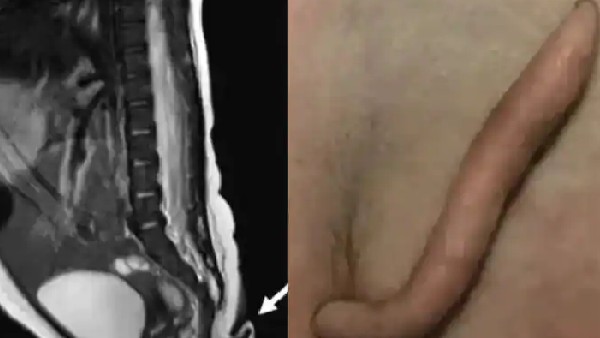

2 ಇಂಚು 'ಬಾಲ'ದೊಂದಿಗೆ ಜನಿಸಿದ ಮಗು: ಫೋಟೋ ವೈರಲ್

ಮೆಕ್ಸಿಕೋ ನವೆಂಬರ್ 28: ಹೆಣ್ಣು ಮಗುವೊಂದು 2 ಇಂಚು ಉದ್ದದ ಬಾಲದೊಂದಿಗೆ ಜನಿಸಿರುವ ಅಪರೂಪದ ಘಟನೆ ಈಶಾನ್ಯ ಮೆಕ್ಸಿಕೋದಿಂದ ವರದಿಯಾಗಿದೆ. ವೈದ್ಯರು, ನರ್ಸ್ಗಳು ಮಾತ್ರವಲ್ಲದೆ ಪೋಷಕರು ಅಚ್ಚರಿಗೊಂಡಿದ್ದಾರೆ. ಬಾಲವನ್ನು ಹೊರತುಪಡಿಸಿ ಶಿಶು ಸಂಪೂರ್ಣವಾಗಿ ಆರೋಗ್ಯಕರವಾಗಿದೆ. ಗರ್ಭಾವಸ್ಥೆಯಲ್ಲಿ ಯಾವುದೇ ತೊಂದರೆಗಳಿಲ್ಲದೆ ಮಗು ಪೂರ್ಣಾವಧಿಯಲ್ಲಿ ಜನಿಸಿದೆ. ತಂದೆ-ತಾಯಿ ಕೂಡ ಆರೋಗ್ಯವಾಗಿದ್ದಾರೆ. ಆದರೂ ಈ ಮಗುವಿಗೆ ಬಾಲವಿರುವುದು ಬೆರಗುಗೊಳಿಸಿದೆ.

ವರದಿಗಳ ಪ್ರಕಾರ, ಎರಡು ತಿಂಗಳ ಹಿಂದೆ ನ್ಯೂವೊ ಲಿಯಾನ್ನಲ್ಲಿರುವ ಆಸ್ಪತ್ರೆಯಲ್ಲಿ ಹೆಣ್ಣು ಮಗು ಜನಿಸಿತ್ತು. ಮಗುವಿಗೆ ಬಾಲವಿರುವುದು ವೈದ್ಯರು ಗಮನಿಸಿದ್ದಾರೆ.

ಬಾಲ ಮೃದುವಾಗಿ 2 ಇಂಚು ಉದ್ದ ಇದ್ದು ಕೂದಲಿನಿಂದ ಕೂಡಿದೆ ಎಂದು ವಿವರಿಸಲಾಗಿದೆ. ಕೆಳಭಾಗಕ್ಕೆ ಕಿರಿದಾಗಿದೆ. ಸುದ್ದಿ ಹೊರಬಿದ್ದ ತಕ್ಷಣ, ಬಾಲದ ಚಿತ್ರಗಳು ಸಾಮಾಜಿಕ ಮಾಧ್ಯಮ ವೇದಿಕೆಗಳಲ್ಲಿ ವೈರಲ್ ಆಗಿವೆ.

ಮಗುವಿಗೆ ಎರಡು ತಿಂಗಳ ವಯಸ್ಸಾದಾಗ, ಆಕೆಯ ತೂಕ ಹೆಚ್ಚಾಗುವುದು. ಬಾಲದ ಬೆಳವಣಿಗೆಯಾಗುವ ಸಾಧ್ಯತೆ ಬಗ್ಗೆ ವೈದ್ಯರು ಅನುಮಾನಿಸಿದ್ದಾರೆ. ಈ ಬಗ್ಗೆ ಮರು-ಮೌಲ್ಯಮಾಪನ ಮಾಡಲಾಗಿದೆ. ಇದರ ಬೆನ್ನಲ್ಲೇ ಚಿಕ್ಕ ಆಪರೇಷನ್ ಮೂಲಕ ಬಾಲವನ್ನು ತೆಗೆಯಲಾಗಿದೆ. ಆ ದಿನ ಯಾವುದೇ ತೊಂದರೆಯಿಲ್ಲದೆ ಹೆಣ್ಣು ಮಗುವನ್ನು ಡಿಸ್ಚಾರ್ಜ್ ಮಾಡಲಾಗಿದೆ ಎಂದು ತಿಳಿದು ಬಂದಿದೆ.

2017 ರ ವೇಳೆಗೆ ಇಂತಹ 195 ಪ್ರಕರಣಗಳನ್ನು ವಿಶ್ವದಾದ್ಯಂತ ಗುರುತಿಸಲಾಗಿದ್ದು, 20 ಸೆಂಟಿಮೀಟರ್ಗಳು (7.9 ಇಂಚುಗಳು) ಬಾಲ ಇರುವ ಮನುಷ್ಯರು ಕಂಡುಬಂದಿರುವುದು ಅತ್ಯಂತ ವಿರಳ ಎಂದು ವರದಿಗಳು ಸೂಚಿಸುತ್ತವೆ. ಹಿಂದಿನ 2021 ರಲ್ಲಿ ಬ್ರೆಜಿಲಿಯನ್ ಮಗುವೊಂದು ಬಾಲದೊಂದಿಗೆ ಜನಿಸಿತ್ತು. ಆದರೆ ಈ ಬಾಲಕ್ಕೆ ಕೊನೆಯಲ್ಲಿ ಚಂಡಿನಾಕಾರದ ಮಾಂಸವಿತ್ತು. ಬಳಿಕ ಅದನ್ನು ತೆಗೆದು ಹಾಕಲಾಯಿತು.